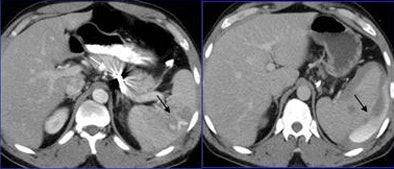

| A 45-year-old man after a car collision (left). Initial axial CT performed after splenic artery embolization (white arrow), shows a round area of increased attenuation in the spleen (black arrow).This finding was believed to represent active bleeding, but organ injury was not visible. Five-minute delayed scan (right) demonstrated intraperitoneal fluid, hematoma, and contrast material extravasation, confirming that the finding was secondary to delayed splenic rupture. The patient subsequently underwent splenectomy. All images and data courtesy of Dr. Alessandro Lemos. |